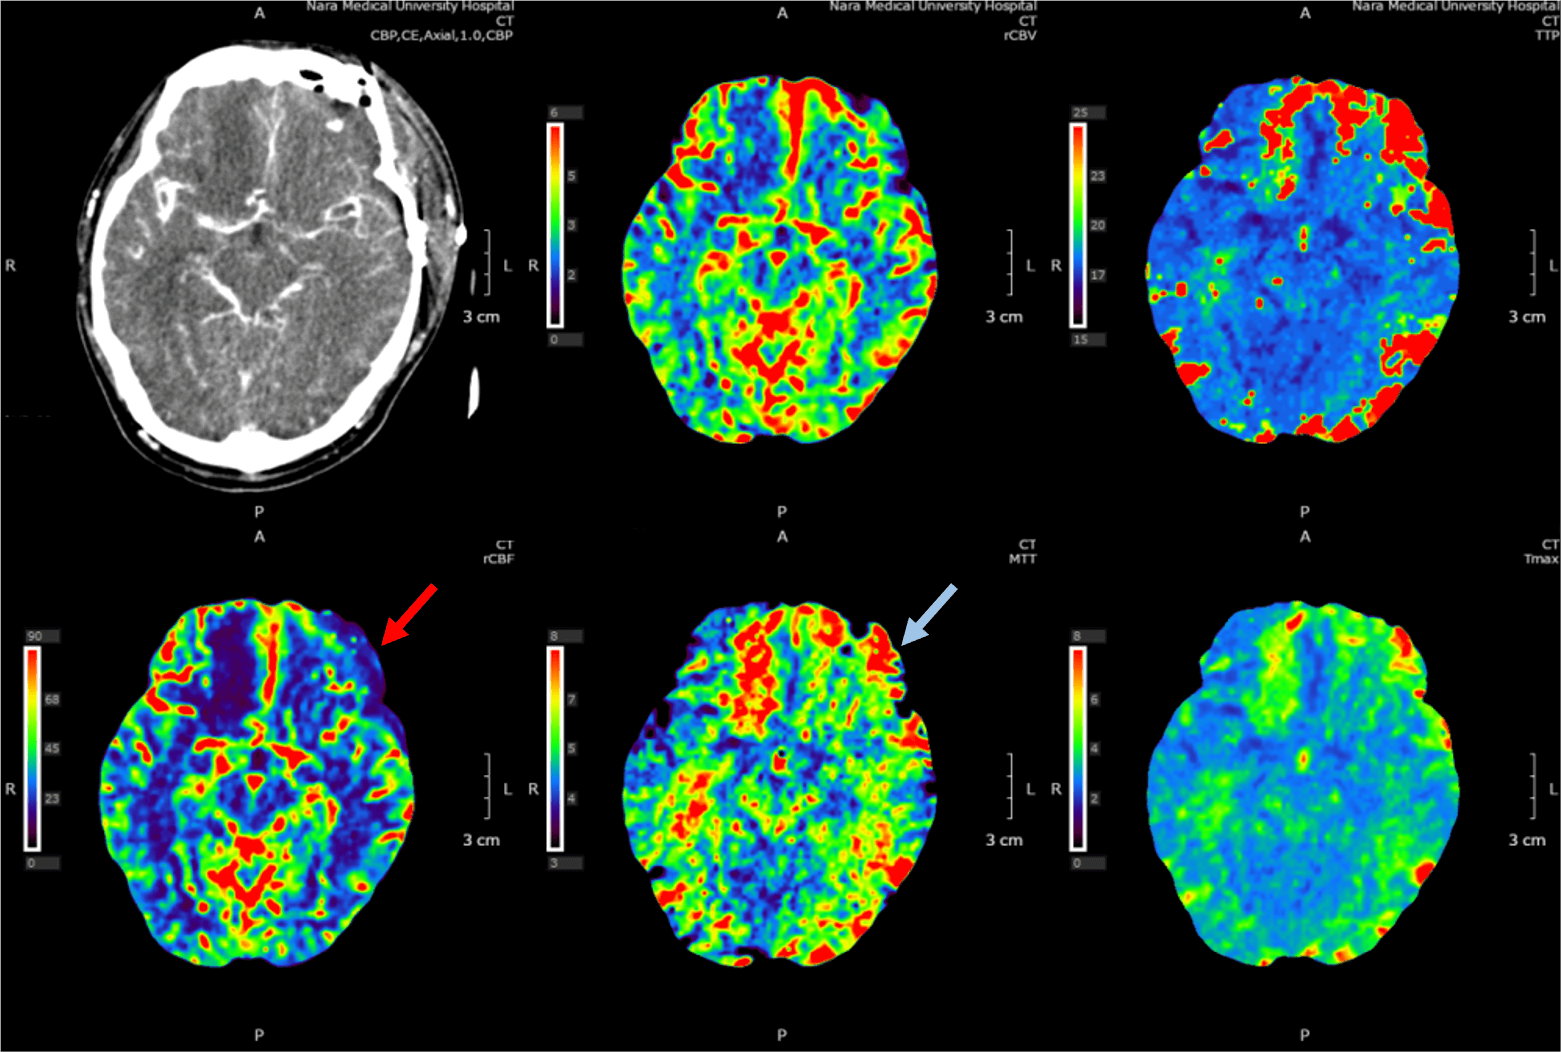

40歳代、男性、60kg、左内頚動脈瘤破裂、クモ膜下出血

左内頚動脈瘤破裂に対しクリッピング術後。術後評価のために頭部CTA、CTV、CT perfusion施行。

CTの結果脳血管攣縮が認められ、ファスジル塩酸塩の動注療法が施行された。その後は増悪なく経過した。

当該疾患の診断における造影CTの役割

くも膜下出血は脳表面の血管が破綻して生じる緊急疾患であり、迅速な診断と適切な治療を行わなければ重篤な転帰を辿る。予後を悪化させる因子としては再出血や遅発性脳血管攣縮が重要であり、特に再出血は高率に予後を不良とするため、治療後も慎重な経過観察が求められる。

造影CTは、くも膜下出血の術前・術後評価の双方で用いられる。術前では破綻血管の同定や治療計画立案に、術後では再出血の有無や脳血管攣縮の評価に活用される。また発症前であっても、造影CTは動脈瘤の早期検出や血管構築の把握に寄与し、予防的観点からも重要な役割を果たす。

CT技術や撮像プロトコル設定について

術後の血管攣縮評価に有用なCBP法(Cerebral Blood Perfusion)は、同一断面を連続的に撮影するダイナミックスキャンにより、急速静注したヨード造影剤の通過を捉える手法である。本法では脳組織内の毛細血管血流を解析し、脳血流量(CBF)、脳血液量(CBV)、平均通過時間(MTT)などのパラメータをカラーマップとして可視化できる。これにより、血管攣縮の有無を含めた虚血性脳血管障害の定量的評価が可能となる。

急性期SAH患者はしばしば不穏状態にあるため、撮影時間の短縮や体動補正が課題となるが、本検査は1分以内で施行可能であり、簡便性と迅速性の両面から臨床的に重要な検査である。

術前では破綻血管の同定と治療計画に重点を置いたCTA撮影を、術後および経過観察では血管攣縮や虚血評価を目的としたCBP撮影を選択する。これらを組み合わせることで、診断から治療戦略決定、さらには予後予測まで一貫した画像診断が可能となる。